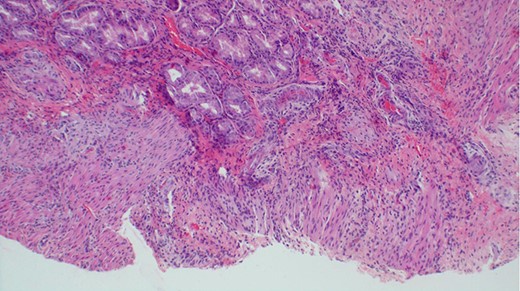

The baby was prepared and taken for an emergency laparotomy whereby intraoperatively, a gastric perforation was found measuring 0.5 by 0.5 cm, circumferential and located on the anterior aspect of the stomach body near the pylorus (Fig. 2). There was also about 50 ml of amber-colored ascites. The perforation was repaired and Grahm’s patch was put, thorough abdominal lavage and the abdomen was closed in layers. Biopsy from the perforation site revealed non-necrotizing mild chronic gastritis, not otherwise specified with ulcerations (Figs 3 and 4).

Histological appearance of gastric wall showing ulceration, mild chronic inflammation, focal hemorrhage and serosal fibrosis (H&E staining, ×20).